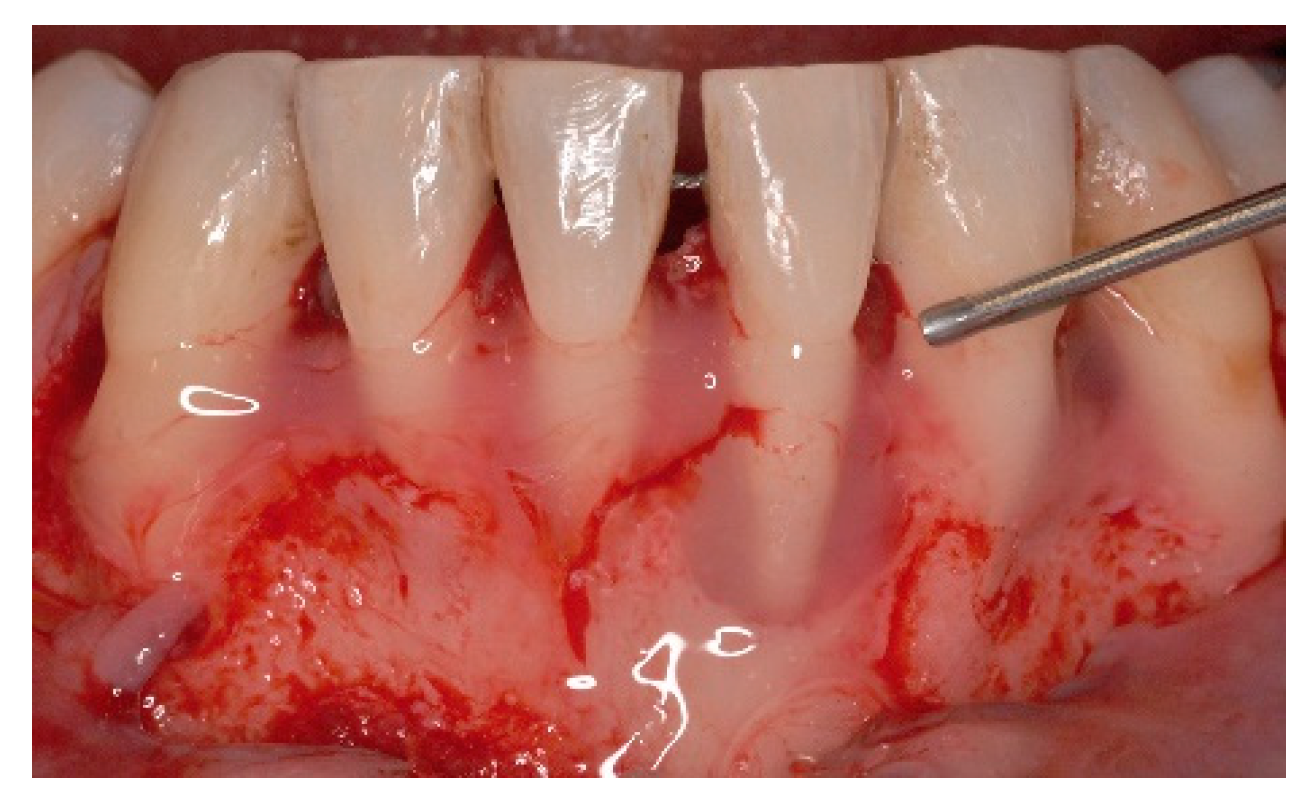

4. Free Connective Tissue Grafts in Periodontal Regenerative Procedures

5. Materials and Methods